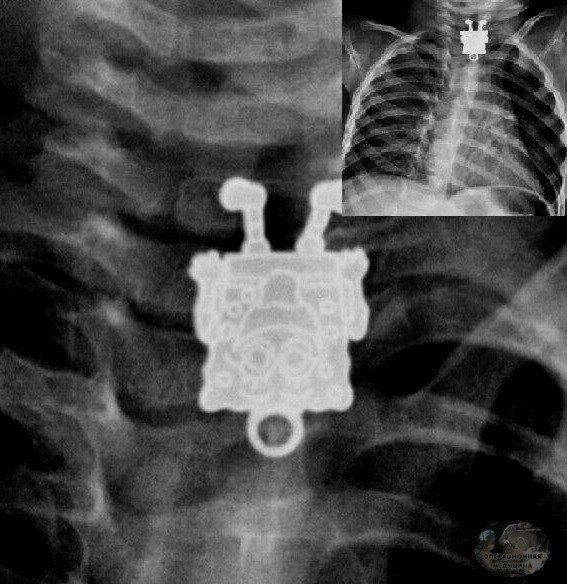

Рентгеновский снимок 16-месячного маленького пациента.

По результатам исследования стало известно, что ребенок проглотил кулон в форме губки боба